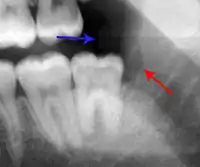

| Pericoronitis associated with the lower right third molar (wisdom tooth). | |